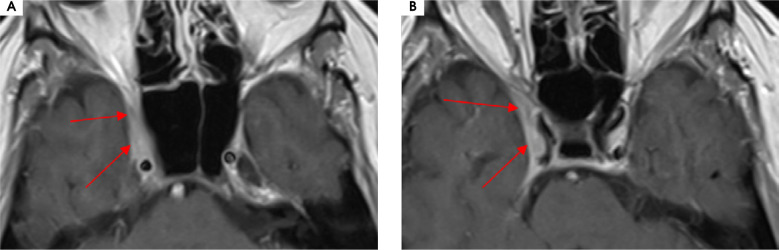

Purpose: Tolosa-Hunt syndrome (THS) is a rare cause of painful ophtalmoplegia with different clinical manifestations. It is described as a unilateral periorbital headache with concomitant dysfunction of at least one out of the IIIrd, IVth and VIth cranial nerves due to the granulomatous inflammation of periorbital structures, but no underlying cause has been established.

Case description: We present six patients referred to the Neurology Department due to a unilateral headache with ipsilateral paresis of at least one cranial nerve responsible for eye movements. The THS diagnostic criteria of the International Headache Disorders Classification (ICHD-3) were applied and analysed. Few patients had atypical clinical manifestations according to these criteria.